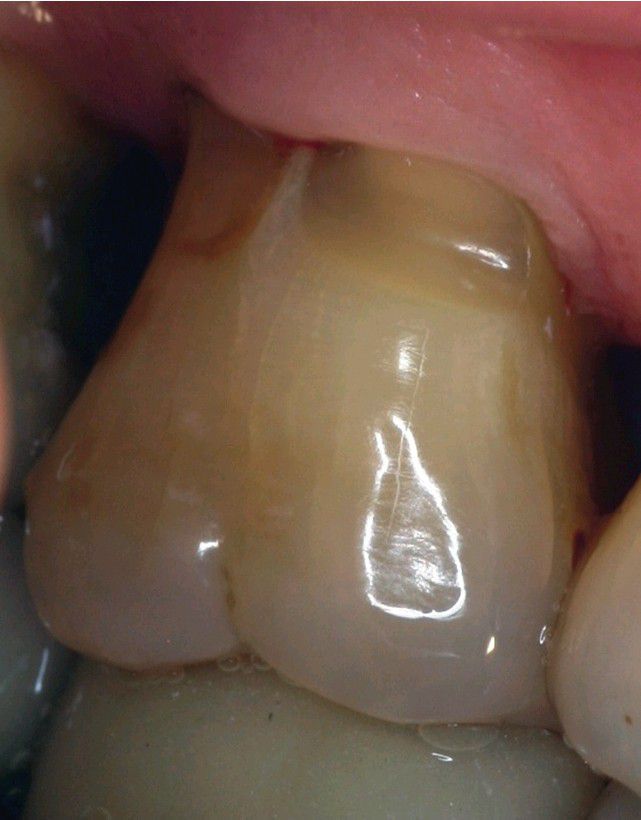

Cervical Enamel Extension

. Flat V-shaped extension of enamel into the bifurcation of a maxillary molar.